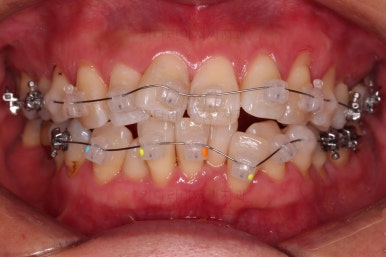

장치를 부착했습니다.

이번 환자분이 선택한 장치는 데이몬 클리어라고 하는 현존하는 자가결찰 세라믹 장치 중에 가장 심미적인 장치입니다.

사실상 멀리서 보면 철사를 제외하고는 거의 눈에 띄지 않는 모습인데요.

단점은 부피가 다른 장치들보다 약간은 더 크기 때문에 입이 약간 더 나와보일 수 있다는 점이죠.

작은 어금니를 발치하고 치열을 가지런하게 해줍니다.

아직 아래 앞니에 있는 유치는 발치하지 않았는데요.

현 상태로 발치를 하게 되면 기구 접근이 되지 않아 광범위하게 뼈를 갈아내며 뽑아야 됩니다.

교정을 하면 기구 접근이 충분히 되도록 공간을 벌린 뒤 발치를 할 수 있어 기간은 더 걸릴 수 있겠지만 잇몸뼈를 보존하고 수월하게 발치를 하려면 교정만한게 또 없죠.